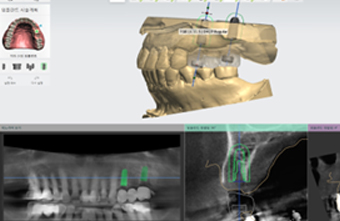

3D CT 분석으로 이식 범위·각도 사전 계획

전체 임플란트는 상·하악 전체 치아가 상실되었을 때, 디지털 정밀 진단 → 최소한의 심기 → 고정형 보철 연결을 통해 자연 치아 기능과 심미성을 회복하는 디지털 기술력 기반의 치료입니다.